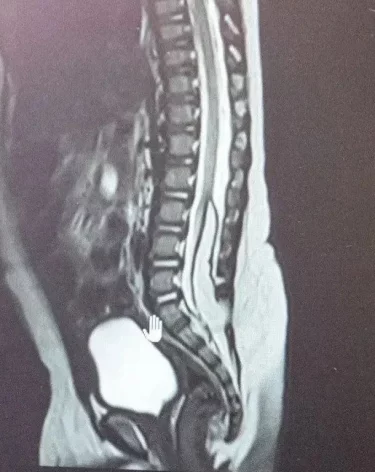

В Кемерове медики областной детской больницы с начала года спасли двух детей со сложными врождёнными аномалиями. Одному пациенту было 8 месяцев, другому – 6, рассказали в минздраве Кузбасса.

У обоих детей выявили липомиелоцеле – редкую аномалию, при которой патологическая жировая ткань формируется в спинном мозге, фиксируя его. Из-за этого нарушается развитие и рост как самого спинного мозга, так и тазовых органов, у детей происходит недержание.

В обоих случаях нейрохирурги провели сложные ювелирные операции, удалив новообразования. Теперь новорождённые могут расти и развиваться, как обычные дети.